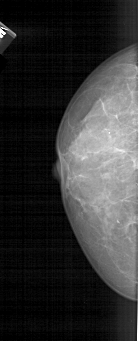

A_1431_1.LEFT_CC

LEFT_CC LINES 4771 PIXELS_PER_LINE 1951 BITS_PER_PIXEL 12 RESOLUTION 43.5 NON_OVERLAY